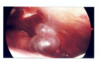

Purpose of Bronchoscopy (Flexible & Rigid):

To vizualise the upper airway as well as distal anatomies in the trachea and bronchi

Flexible => flexible scope

Rigid => Stiff scope like

Flexible BRONCHOSCOPY:

Diagnostic procedure

Commonly performed prior to lung resection to reconfirm diagnosis, or to determine the invasion or obstruction of the distal airway

Allows for distal airway examination

Rigid BRONCHOSCOPY

Diagnostic procedure

Procedure of choice for tracheal stenosis (tracheal dilation), airway obstruction, foreign body removal, and massive hemoptysis